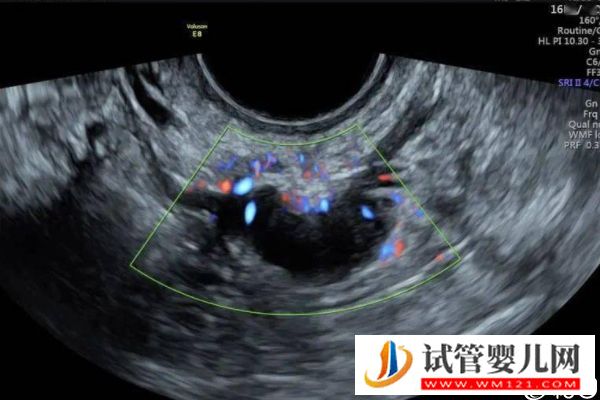

- 取卵后移植前要密切監(jiān)測(cè)自己的內(nèi)膜情況,相因建議各位要遵醫(yī)囑按時(shí)到醫(yī)院做全面檢查,如B超檢查、激素水平檢測(cè)等,在子宮內(nèi)膜環(huán)境適宜的情況下,才可以安排胚胎移植手術(shù)。如果宮腔環(huán)境差,容易造成胚胎著床失敗。